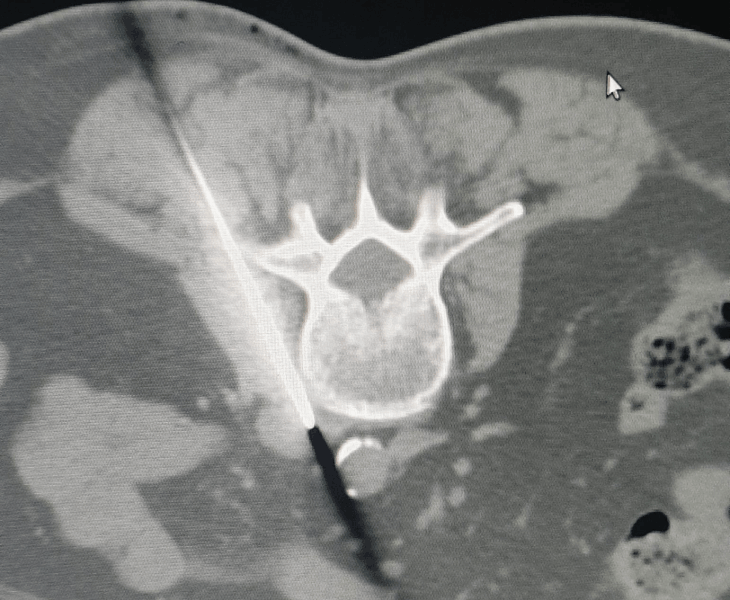

CT‑Guided Pelvic Biopsy

Accurate tissue sampling from deep pelvic lesions with CT guidance.

- CT‑guided biopsy of pelvic lesions